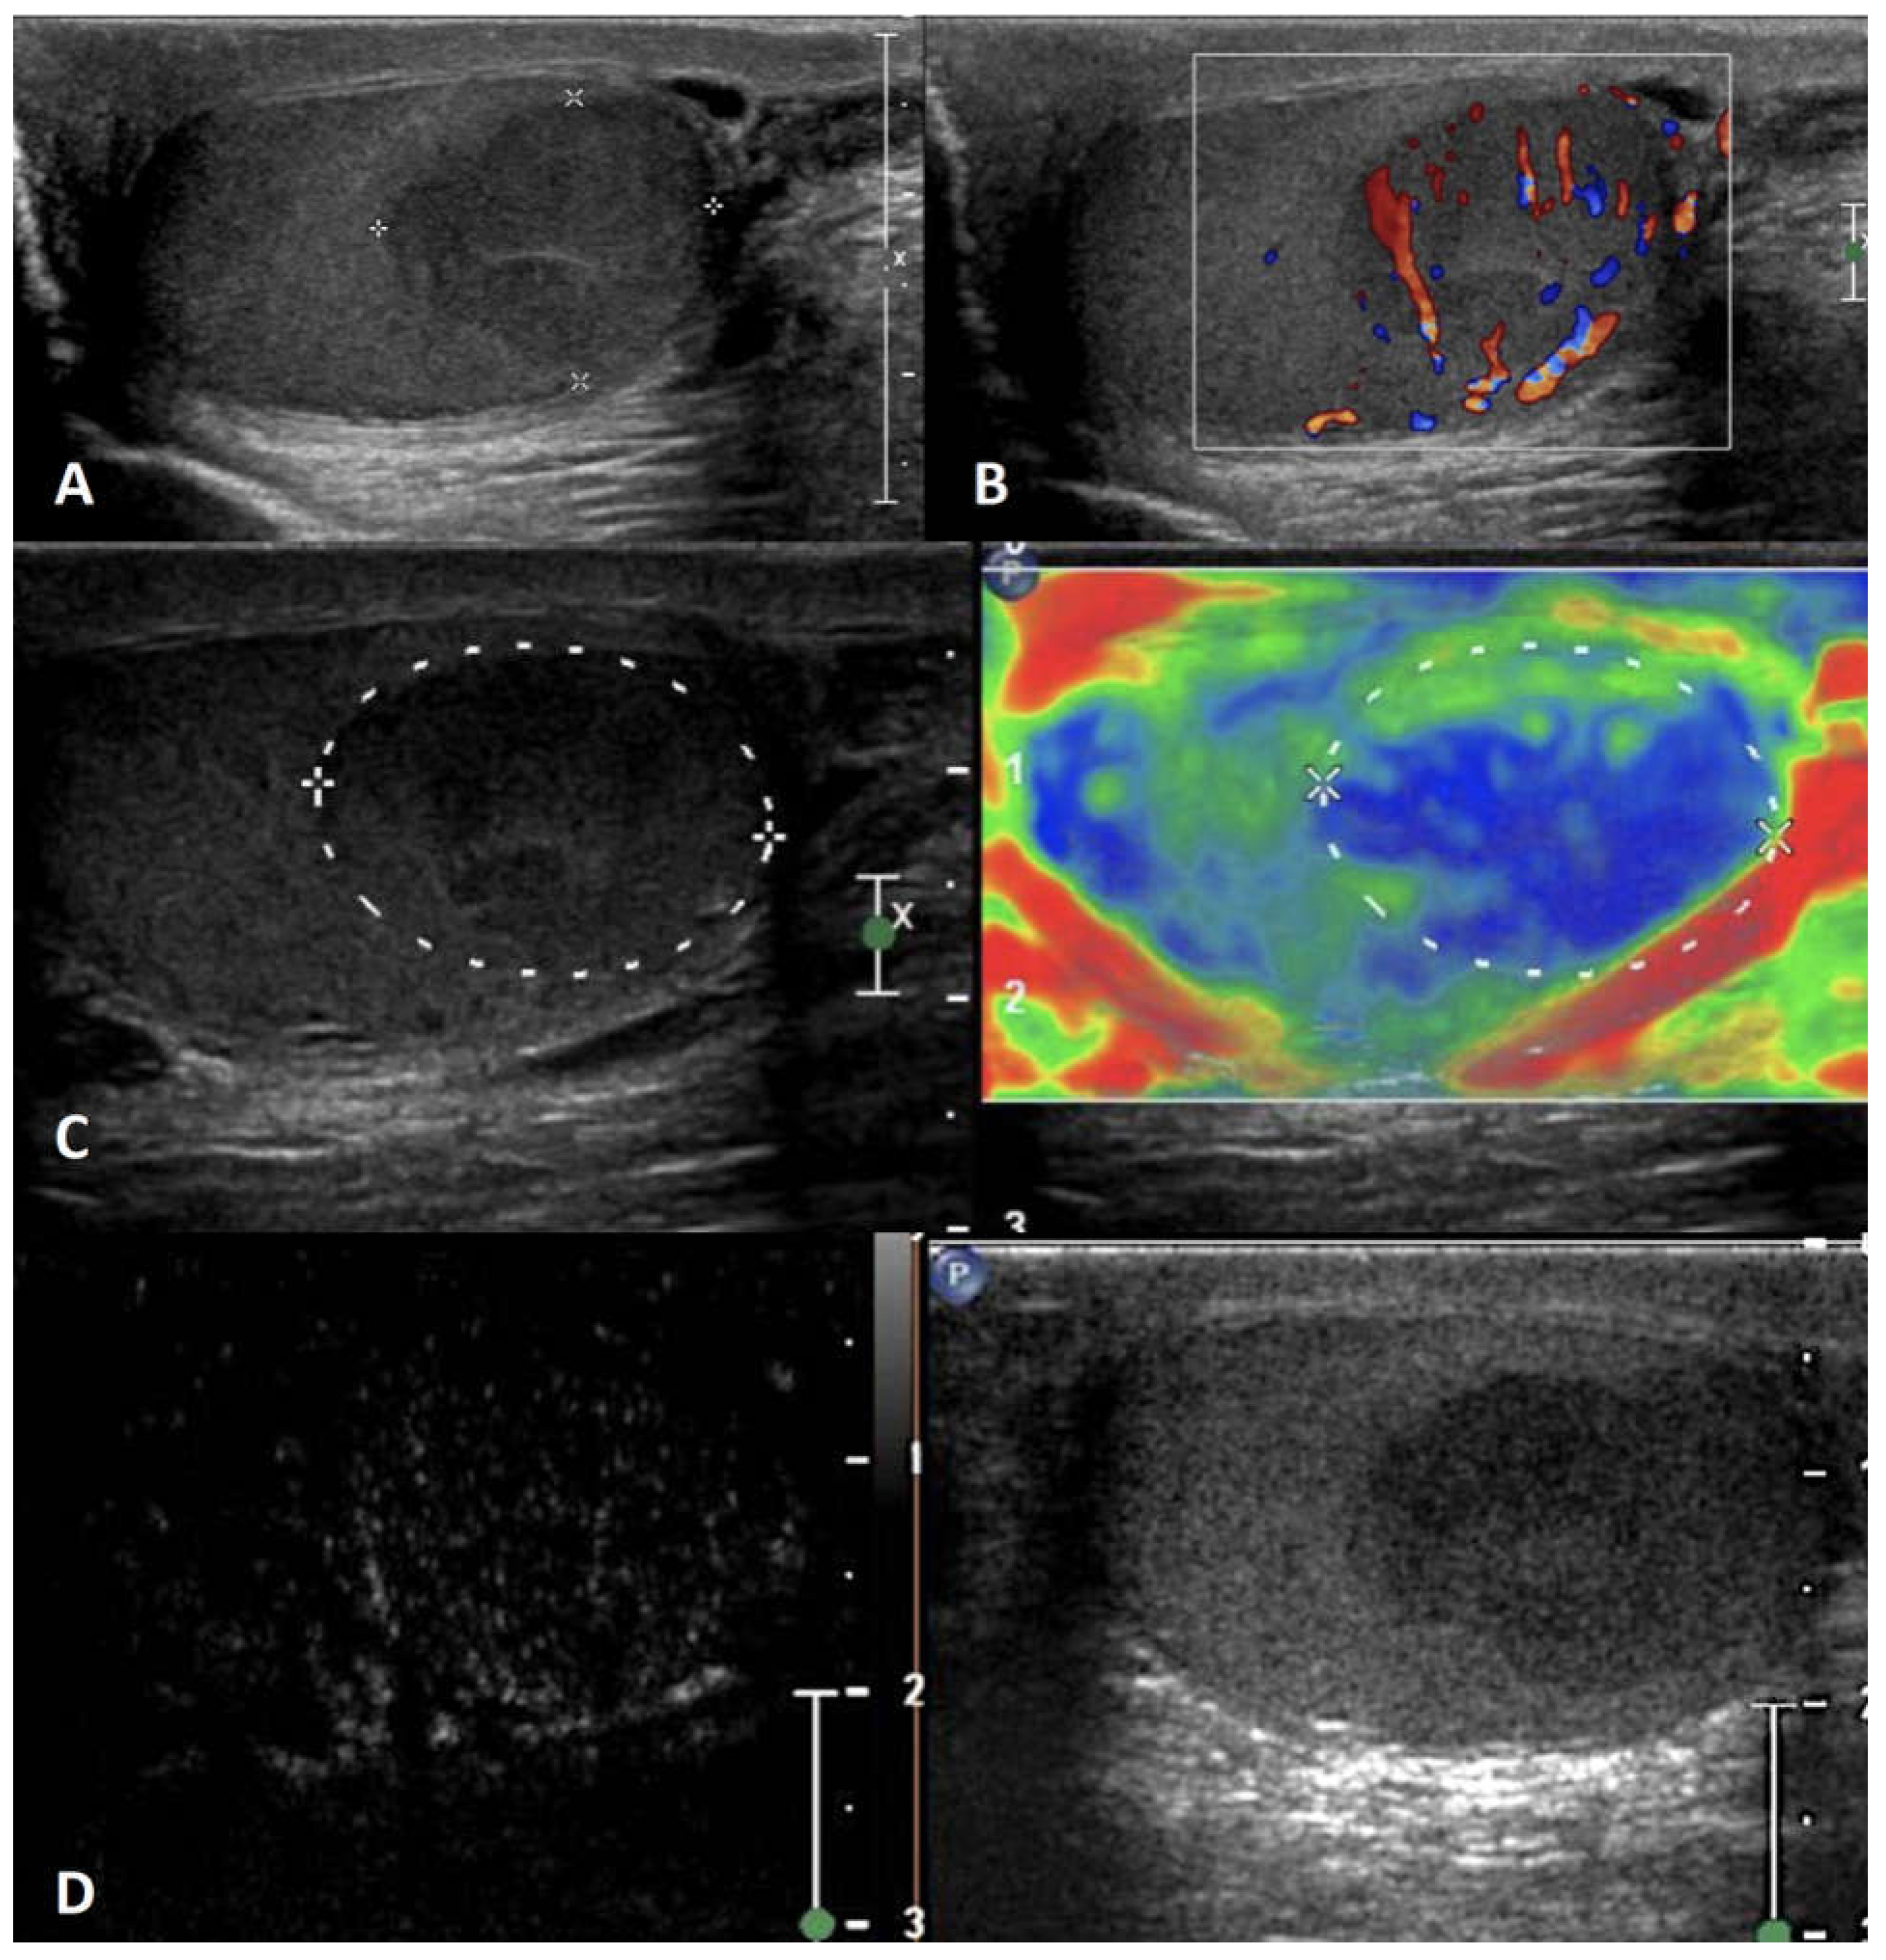

5.3. Testicular Adrenal Rest Tumors (TARTs)

| Non-neoplastic intratesticular lesions | |||||

| Clinical presentation | GSUS | CDUS | CEUS | SE | |

| Adrenal rest | patients with CAH; usually not palpable |

hypoechoic lesions with irregular margins, hyperechogenic foci, typically localized in the mediastinum testis, usually bilateral | markedly vascularized |

hyperenhanced | hard lesions with low/absent elastic strain |

5.5. Segmental testicular infarction

| Segmental infarction | idiopathic or consequent to surgery, inflammatory events, blood disorders or autoimmune diseases; usually acute painful swollen scrotum (but also asymptomatic cases) | hypoechoic wedge-shaped or roundish area | Avascular or peripheral rim of low CD |

unenhanced/ perilesional rim enhancement |

soft lesions with high elastic strain |